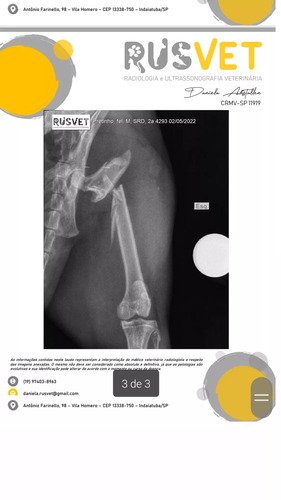

Meu nome é Mariana, um dos meus filhos de patas, meu gato chamado Pretinho foi atropelado, corri com ele pro veterinário, fizemos raio x e ele ficou internado. O raio x deu 2 fraturas no femur onde ele passará por uma cirurgia no valor de 2207$ como na imagem em anexo. O pouco pra Deus eh muito e pra nos tambem, qualquer valor que puderem ajudar ja vai fazer muita diferença pra nos, ja que fora a cirurgia ja gastamos em torno de 600 reais e não temos condição de arcar com tudo, mas independente do valor nao deixamos de dar a ele todos os cuidados veterinarios necessarios !!! Agradeço de coração desde ja 😭🙏🏻